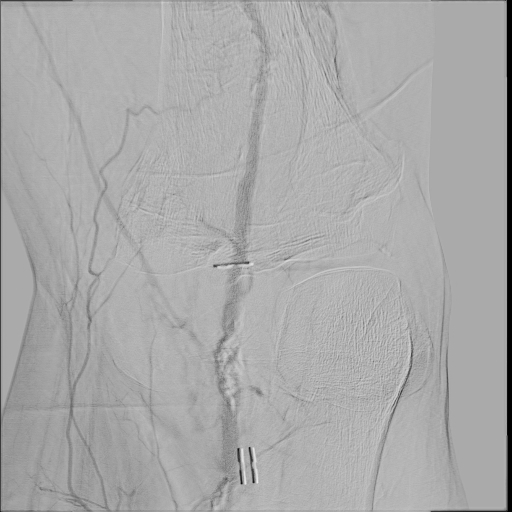

Owning to multiple stenosis and total occlusion, terumo wire cannot pass through the lesion. we ever use Connect wire, V-18 wire and even shift to Astato for calcified lesion with the assist of CXI. After several times attempt of antegrade wiring, the V-18 wire finally pentrate thrthrough the calcified lesion and advanced to distal popliteal artery. Finally the V-18 wire pass the lesion and balloon angioplasty was performed. Diffuse dissection with TIMI II flow was discovered after balloon angioplasty, thus we deployed Supera stent at SFA.Final angiogram showed acceptable result.